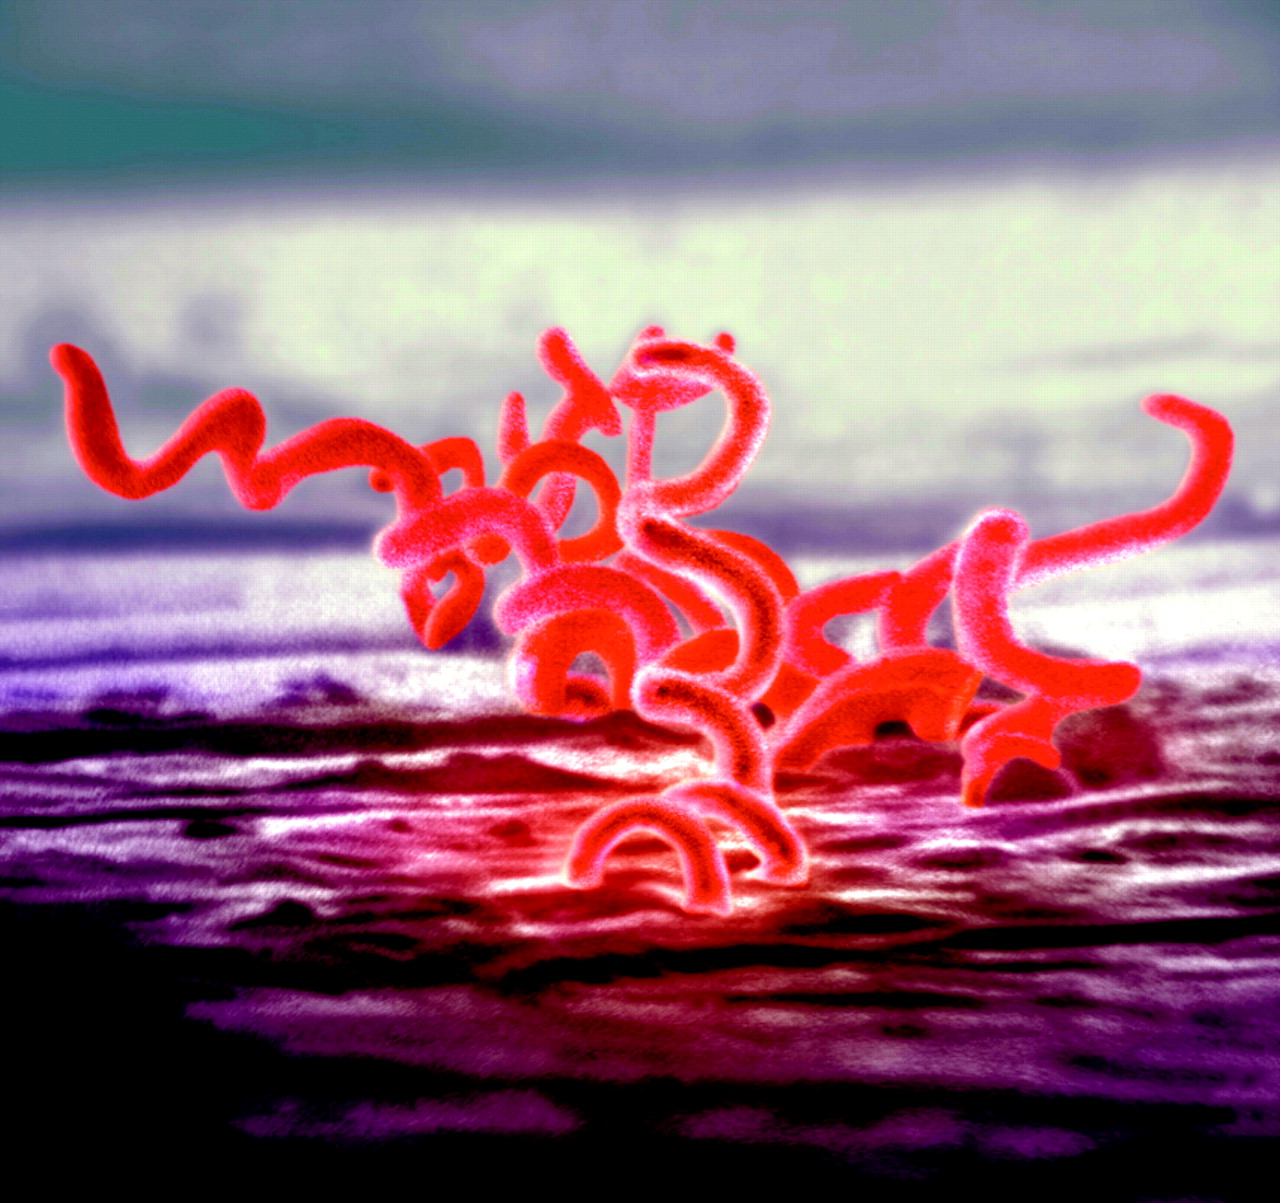

Bakteri Sipilis | Microbiología, Enfermedades de transmision, Enfermedades

Bakteri Sipilis | Microbiología, Enfermedades de transmision, Enfermedades